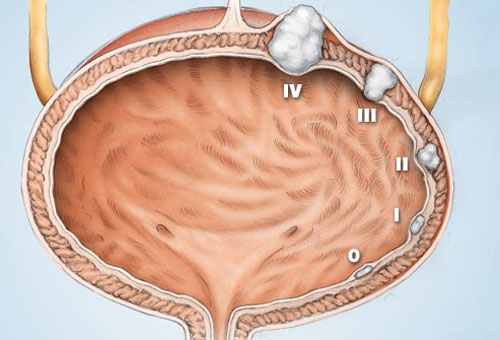

Các giai đoạn của ung thư bàng quang

Giai đoạn 0 : Ung thư ở lại trong lớp lót bên trong.

Giai đoạn I: Ung thư đã lan đến bàng quang.

Giai đoạn II : Ung thư đã đạt đến mức cơ của bàng quang.

Giai đoạn III: Ung thư đã lan rộng đến các mô mỡ xung quanh bàng quang.

Giai đoạn IV: Ung thư đã lan đến thành vùng chậu hoặc bụng, hạch bạch huyết, hoặc lan tới xương, gan hay phổi.

Ung thư bàng quang phát triển qua 5 giai đoạn